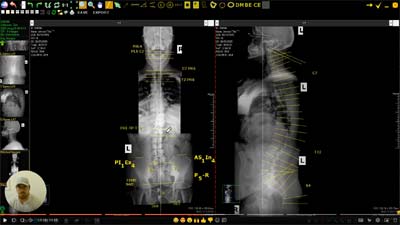

My first visit was X-rays and some other equipment used to collect data on my body’s condition. Dr. Craig would later review that data and put together a plan to get me back to the best version of me possible. This plan came in the form of a personalized video. Is the video YouTube entertainment quality? No. It’s a single take of Dr. Craig analyzing the X-rays and data. He explained what’s going on with my body and his plan on how he can fix it. I have no medical training. Seeing the condition of my back in the X-rays revealed that aha moment; yes, this is why I have felt the way I have felt.